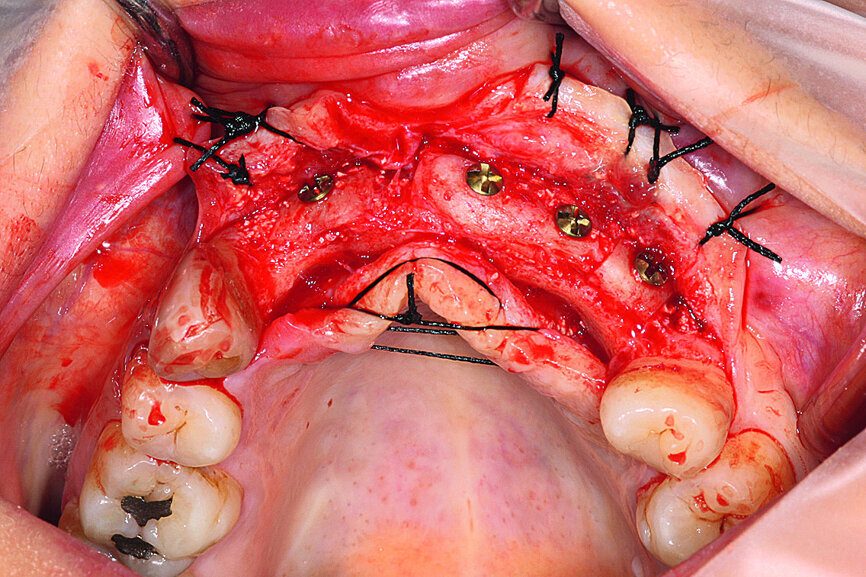

Fig. 13: The reopened site showing correct graft integration, a notable increase in cortical bone and excellent vascularity.

Fig. 16: All five implants equipped with threaded cover screws and the surrounding tissue sutured.

Fig. 17: Loaded implants, healing abutments in situ.